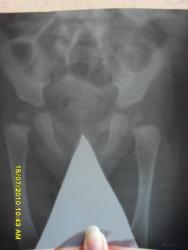

Здравствуйте! Моей дочери 4.5 месяца поставили диагноз дисплазия тазобедренных суставов. На ренгене в прямой проекции определяется: ацетобулярный угол справа 30 град., слева 28 град. Угол Виберга справа 12 град., слева 20 град. Оссификация головок соответствует возрасту, но контуры их неровные. заключение: уменьшение углов Виберга указывает на уплощение впадин с обеих сторон. Подскажите пожалуйста что нужно делать в данной ситуации.

При оценке рентгенограммы таза вашей дочери патологических признаков не обнаружено. Все симптомы играют значение вместе, в общем комплексе, единичные легкие проявления обычно отбрасываются.   Но думаю, что нужно динамическое наблюдение у детского ортопеда - травматолога...

В оценке состояния тазобедренных суставов у детей данной возрастной группы используются следующие основные рентгенологические показатели:1. ацетабулярный индекс   2. центрация продольной оси основания шейки бедренной кости на свод впадины (в норме должно пересекать свод впадины в области медиальной четверти). Все это имеет силу только при правильной укладке, в среднем положении. Угол Виберга безусловно важный параметр, ну никак не в этой возрастной группе (т.к. требует определения истинного центра головки бедренной кости, а ядро оссификации не является этим центром). В заключении- диагноз дисплазии только по данным рентгенологического обследования не ставится, это комплексный диагноз.

При желании, можно увидеть легкие признаки дисплазии, но специализированного ортопедического лечения Ваш ребёнок не требует. Ортопед может назначить ЛФК, физиотерапию и другие "пляски с бубнами".

Необходим рентгенконтроль в возрасте 1 год.

Дочери сейчас 7 месяцев. Сделали новые снимки. Ортопед выписал Шину Валенского I. Скажите,пожалуйста необходимо ли ее носить в данной ситуации?

sdc16105.jpgsdc16106.jpgsdc16107.jpg

Никакие шины не нужны.

Извините за назойливость, а есть какие-нибудь изменения по сравнению с предидущими снимками? ну кроме того что дочь выросла)

Кроме того, что ребёнок вырос - нет. Суставы с признаками перенесенной дисплазии легкой степени. В ортопедическом лечении ребёнок не нуждается.